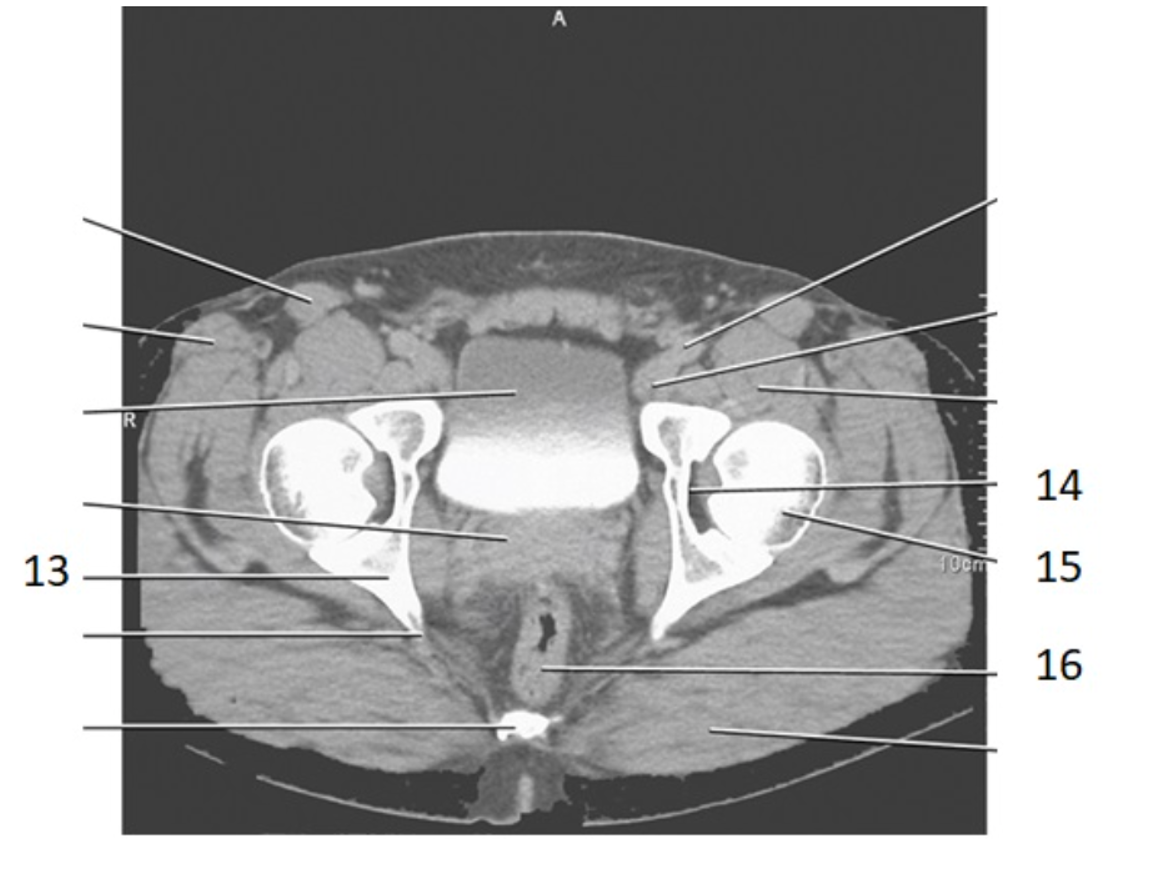

15

femoral head

14

acetabulum

17

pubic bone

pubic symphysis